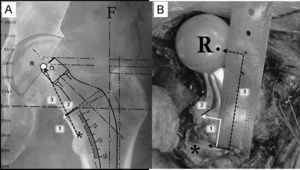

Para reproducir intraoperatoriamente la posición del vástago femoral y determinar el nivel de la osteotomía del cuello deben registrarse 3 medidas utilizando la regla magnificada que suele encontrarse en las plantillas de magnificación seleccionada (fig. 5A). La primera es la distancia entre el vértice proximal del trocánter menor y la zona medial de la osteotomía cervical. Esta medida es fundamental para determinar intraoperatoriamente el nivel de osteotomía cervical. La segunda medida es la distancia entre el vértice proximal del trocánter menor y el centro de rotación de la cabeza femoral protésica seleccionada. Esta medida es fundamental para reproducir el offset y la longitud del miembro elegida. Finalmente, se calcula la distancia entre la parte más medial del cuello femoral y la zona de implantación del vástago femoral a la altura de la osteotomía cervical. Esta tercera medida es fundamental para evitar una posición del tallo en varo o valgo.

A) En esta imagen radiográfica se muestra la forma de calcular las distancias de referencia de la planificación del componente femoral. 1: distancia entre el ángulo superior del trocánter menor y la zona de osteotomía del cuello femoral; 2: distancia entre la zona medial de la osteotomía femoral y el vástago; 3: distancia entre el ángulo superior del trocánter menor y el centro de rotación de la cabeza protésica. B) Imagen intraoperatoria que muestra la forma de reproducir las medidas radiográficas de referencia sobre el fémur del paciente, tras la colocación de los componentes de prueba. Tras la identificación del centro de rotación de la cabeza femoral de prueba, del ángulo proximal del trocánter menor y del borde medial de la osteotomía cervical se utiliza una regla estéril para calcular las distancias previamente descritas (6A). *: zona proximal del trocánter menor; F: eje de la diáfisis femoral; R: centro de rotación de la cabeza protésica.

El posicionamiento adecuado de la pelvis en la mesa operatoria reduce la variabilidad en la orientación del componente acetabular. Tras el abordaje quirúrgico se localiza el ángulo proximal del trocánter menor y se marca la distancia planificada de la osteotomía (fig. 5A). En ocasiones, la línea de fractura puede estar por debajo del nivel de la osteotomía cervical planificado; en estos casos, el cirujano deberá realizar las modificaciones de técnica quirúrgica o implante necesarias para reproducir la distancia entre el trocánter menor y el centro de rotación femoral.

Una vez introducido el vástago femoral de prueba de tamaño, offset y longitud de cuello elegidos, se debe medir la distancia entre el vértice superior del trocánter menor y el centro de rotación de la cabeza femoral (marcado con rotulador) (fig. 5B). Si esta distancia no coincide con la planificada deben hacerse los ajustes necesarios (offset, longitud de cuello y altura del vástago) para lograr reproducirla intraoperatoriamente.